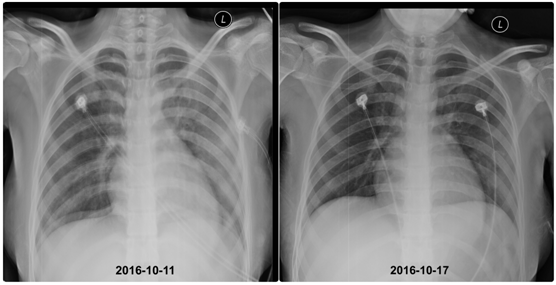

血红蛋白仅为正常参考值的四分之一,血小板为4X10^9/L(正常参考值为100-300X10^9/L),随时都有脏器出血的风险。血气分析提示I型呼吸衰竭,胸片存在双肺弥漫性渗出,肺部CT可见双肺部多发高密度影。

第4天,复查胸片,双肺部渗出影明显吸收;

第9天,肺部CT提示双肺高密度影显著吸收,血红蛋白逐渐上升至70g/L,血氧分压正常。